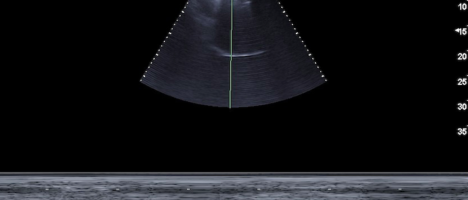

Nella nostra U.O. l’ecografia del polmone riveste un ruolo fondamentale da molti anni sia per lo studio del parenchima, in particolar modo nelle polmoniti interstiziali, ma specialmente per lo studio del diaframma ove permette la valutazione tanto della escursione che del suo ispessimento; per cui nella progressione della riabilitazione appare una arma importantissima, specie nei pazienti nel periodo post intubazione. Tendenzialmente è preferibile posizionare il paziente nel decubito laterale mantenendo l’appoggio del polmone meno compromesso, favorendo in tal senso la ventilazione dell’emitorace maggiormente coinvolto, in più, per favorire la guarigione e prevenire complicanze muscolo-scheletriche dei tessuti molli e lesioni cutanee. Altro fondamentale è evitare la postura Slumped (scivolata nel letto), favorendo un corretto posizionamento in posizione semi-seduta o seduta (30-45°). E’stato inoltre necessario riabilitare i pazienti nel PP dalla posizione supina/semi supina alla posizione seduta a bordo letto, e quando le condizioni lo hanno permesso anche dalla posizione seduta alla stazione eretta con supporto. Questo si è reso fondamentale per ridare parte dell’autonomia che a causa della malattia è andata persa; inoltre dal punto di vista della capacità polmonare determina un miglioramento dei volumi polmonari, basta pensare che dalla posizione supina a quella eretta c’è un guadagno pari a 1L di volume polmonare. Al posizionamento posturale sono state associate strategie di reclutamento personalizzate come esercizi di controllo della respirazione con espansione del torace. L’allenamento dei muscoli respiratori è iniziato a bassa intensità e la sua progressione è stata guidata dalla dispnea/affaticamento (scala di Borg per dispnea e tasso di sforzo percepito) e dal monitoraggio della pressione sanguigna e SpO2. Altro punto cardine del programma di RP è stata la mobilizzazione precoce e l’esercizio aerobico a bassa intensità (<3.0 MET) con progressivo aumento del carico di lavoro in base ai sintomi soggettivi. Durante le sessioni di esercizio sono state valutate la fatica e la dispnea oltre che la valutazione della desaturazione dell’ossigeno indotta dall’esercizio, con integrazione dell’ossigeno con valori di SpO2 <93%.